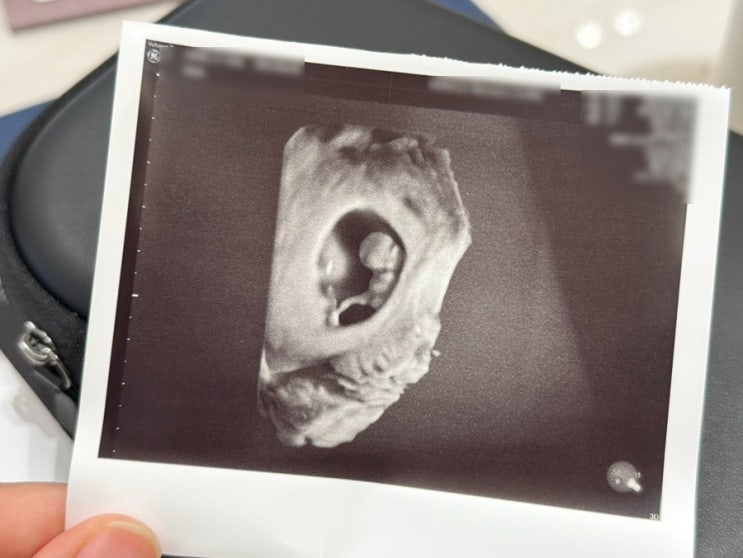

임신일기#6 임신8주차, 9주차, 10주차 증상(시댁 임밍아웃 복권, 8주차 젤리곰)

#임신8주차 #임신9주차 #임신10주차 #복권임밍아웃 #시댁임밍아웃 #임밍아웃시기 #8주차젤리곰 임신8주차 ...